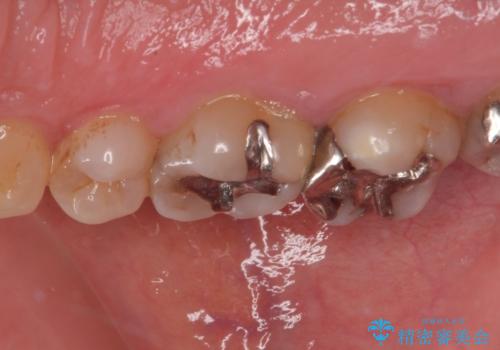

銀歯の下のむし歯 ゴールドクラウンによる補綴治療

- 奥歯で咬んだときに痛みがあり、物が挟まるとのことで来院された患者様です。

咬み合わせが非常に強く、見た目よりも機能と安定性を重視したいとのことで、PGAクラウン(白金加金合金クラウン)にて補綴する治療計画となりました。

PGAクラウンにしたことで咬み心地に全く違和感がなく、気にされていた審美面も、奥歯でありそれほど目立たないこともありますが、白金加金の色を気に入っていただけたので、患者様には大変満足していただけました。